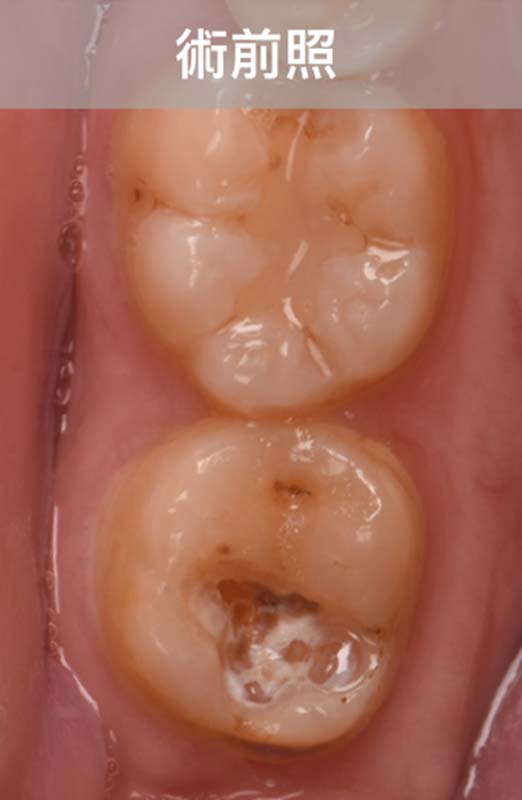

陶瓷嵌體,重建廣泛性蛀牙的下顎第二大臼齒